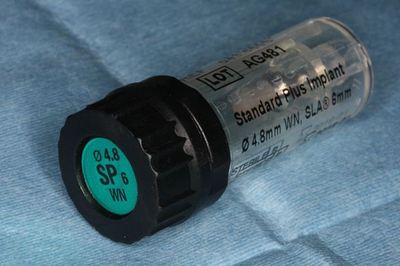

スイスのストローマンインプラントの中でもっとも短い、長さ6mmを選択します。

6mmのインプラントは単独では用いません。

複数のインプラントで歯を作る際にのみ使用できます。

お馴染みのスイスのストローマンインプラントです。

スタンダードプラスインプラント Φ4.8mm WN 6mm